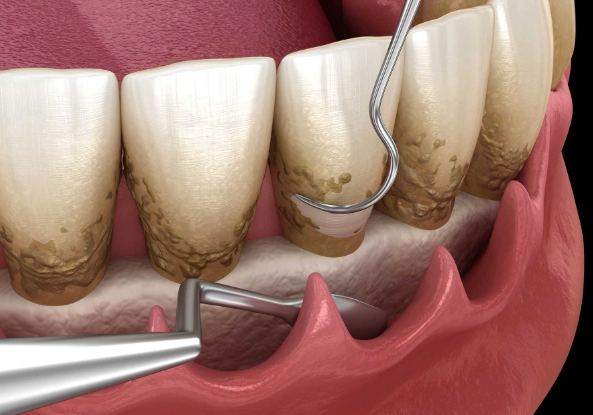

| Periodontal Treatment | A periodontal abscess from gum disease. | Deep cleaning (scaling/root planing) below the gumline to remove tartar and bacteria. | Manages gum disease and the abscess. Requires ongoing periodontal maintenance. |